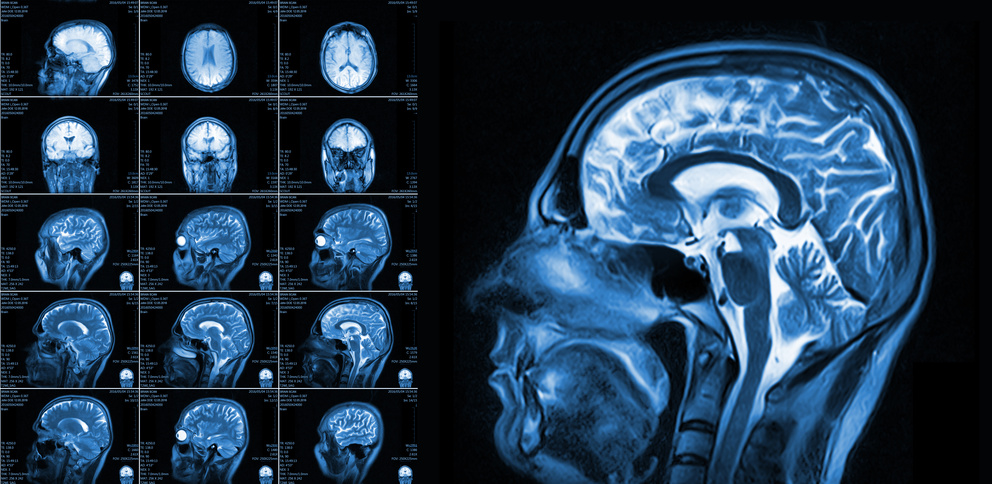

Our babies' brains are being harmed and the science is "clear enough." See this list of some of the science that links fluoride exposure of our babies to their developing brains: